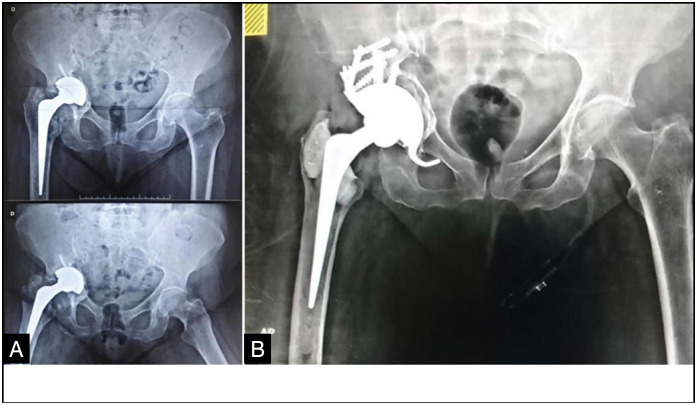

Introduction: Pelvic dissociation is a complex condition with a high rate of surgical complications and no established standard treatment. Surgery aims to preserve limb function by restoring bone structure and hip biomechanics. Conventional orthopaedic implants are made from materials such as stainless steel, cobalt-chrome or titanium. High-porosity implants have been introduced to improve the durability of hip arthroplasty.

Method: A descriptive observational study carried out at the Hospital das Clínicas of the Federal University of Goiás and at the Orthopedics and Traumatology Clinic (COT) in Goiânia. Data was collected from the medical records of patients who underwent total hip arthroplasty between 2012 and 2020, using titanium or tantalum implants, both high-porosity materials.

Results: The study included 26 patients, 53.8% female and 46.2% male. The majority (34.6%) were aged between 60 and 69. Of the patients, 53.8% used titanium implants and 46.2% tantalum. After surgery, 38.5% had a Harris Hip Score between 70 and 80, with 61.5% of patients showing osseointegration in less than six months.

Conclusion: Tantalum, due to its high porosity, was effective in treating patients with pelvic dissociation undergoing revision total hip arthroplasty. Level Of Evidence lV; Descriptive Observational Study .